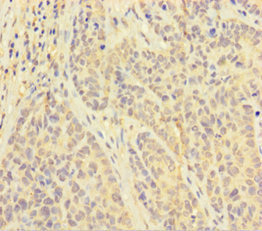

ApplicationsImmunoFluorescence, ELISA, ImmunoHistoChemistry, ImmunoHistoChemistry Frozen, ImmunoHistoChemistry Paraffin

- Applications SupplierELISA(ELISA=1:30-3000), IHC-P(IHC-P=1:100-1:200), IHC-F(IHC-F=1:100-1:200), IF(IF=1:100-1:200)